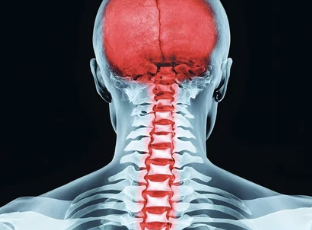

1. 목디스크란? 원인과 특징 이해하기

목디스크는 목뼈 사이에 위치한 디스크가 압박을 받아 탈출하거나 손상되어 발생하는 질환이에요. 디스크가 탈출하면서 신경을 누르게 되어 통증과 다양한 증상이 나타납니다.